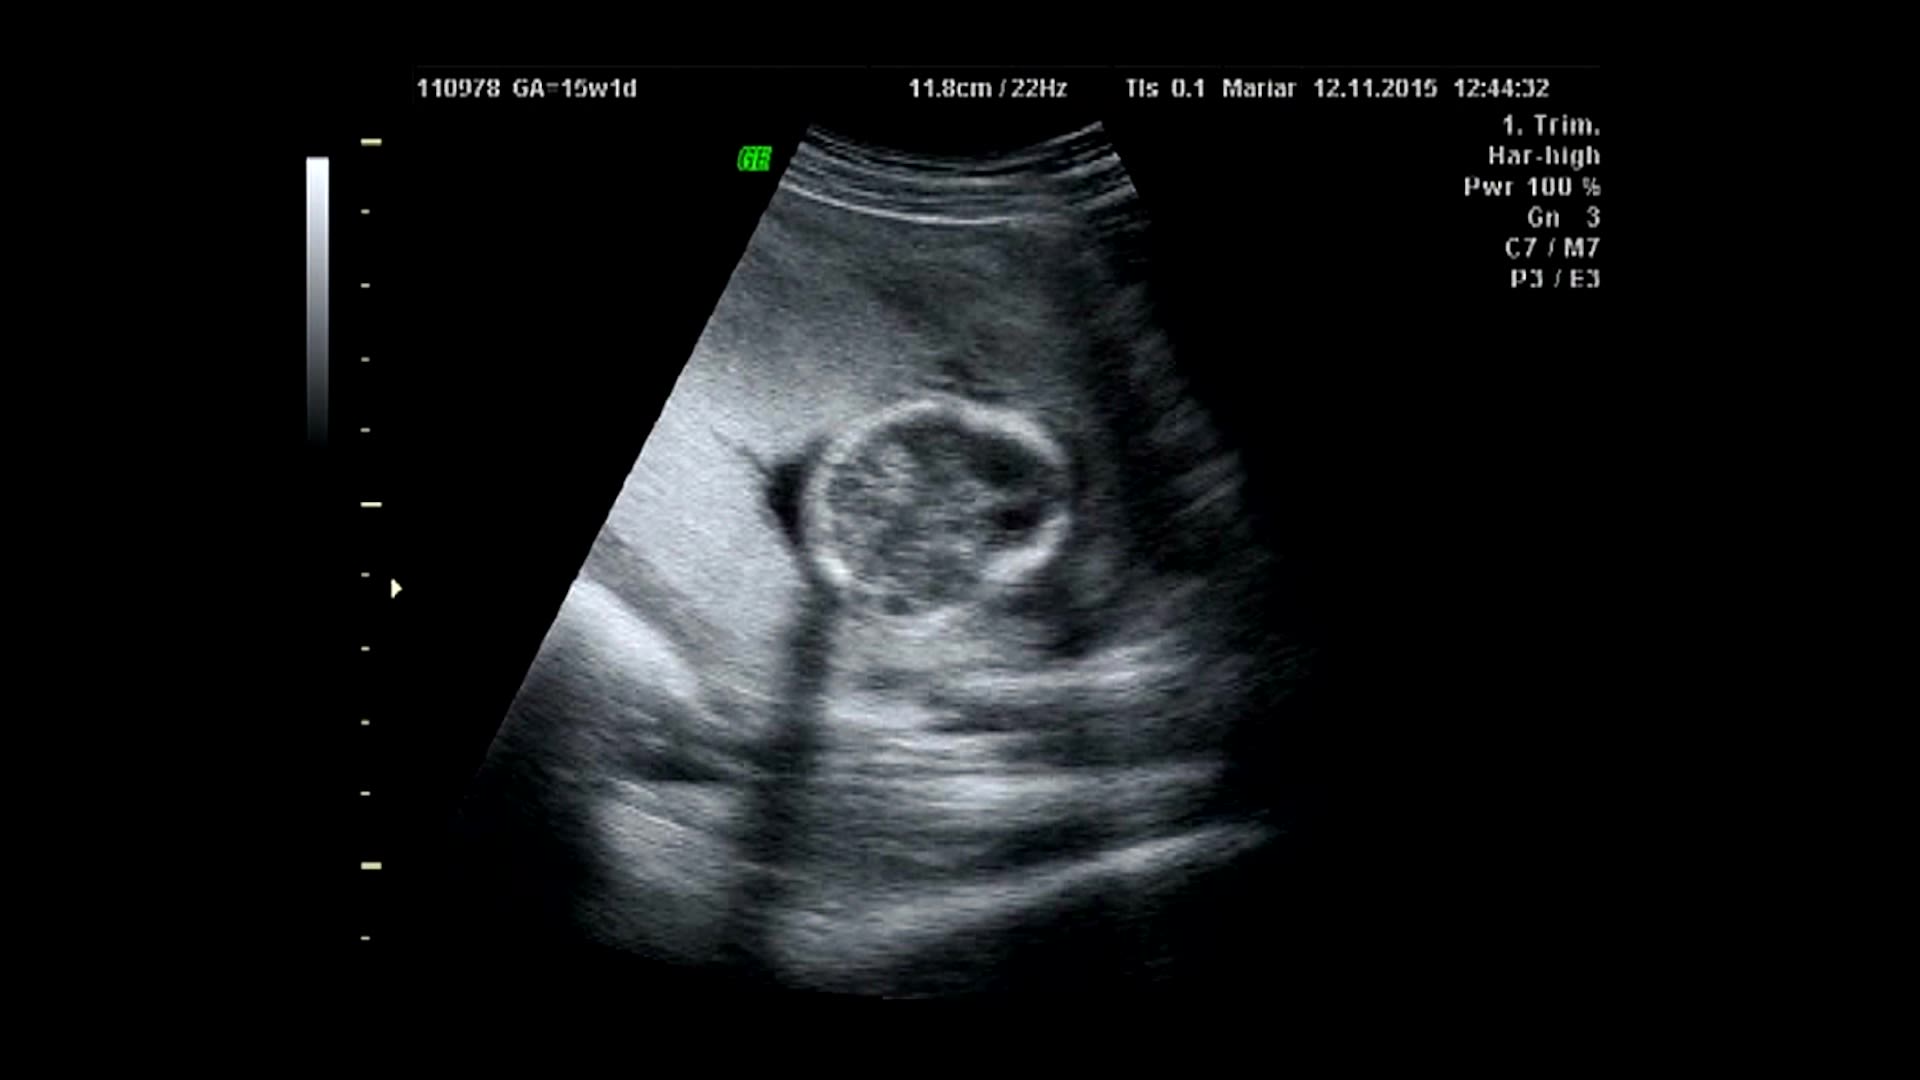

Video with thanks to Professor Mary Rutherford and Evelina London Children's Hospital (Guys' and St Thomas' NHS Foundation).

It has long been known that nutrition, radiation, infections, drugs, and alcohol abuse of the mother during pregnancy can affect an unborn child.

But Professor Molnár explains, mental health problems are far more prevalent than people realise.

He says casually, ‘One in 100, some estimates are even higher, people in the UK have some form of foetal alcohol syndrome (where the mother consumed alcohol while pregnant); it influences the brain development that can later manifest in difficulties with learning, challenging behaviours and mental health problems.

If this syndrome is caught early, he says, it can be corrected somewhat, but it can have a very significant impact on someone’s entire life, ‘They might find it difficult to get a job and live independently as an adult.